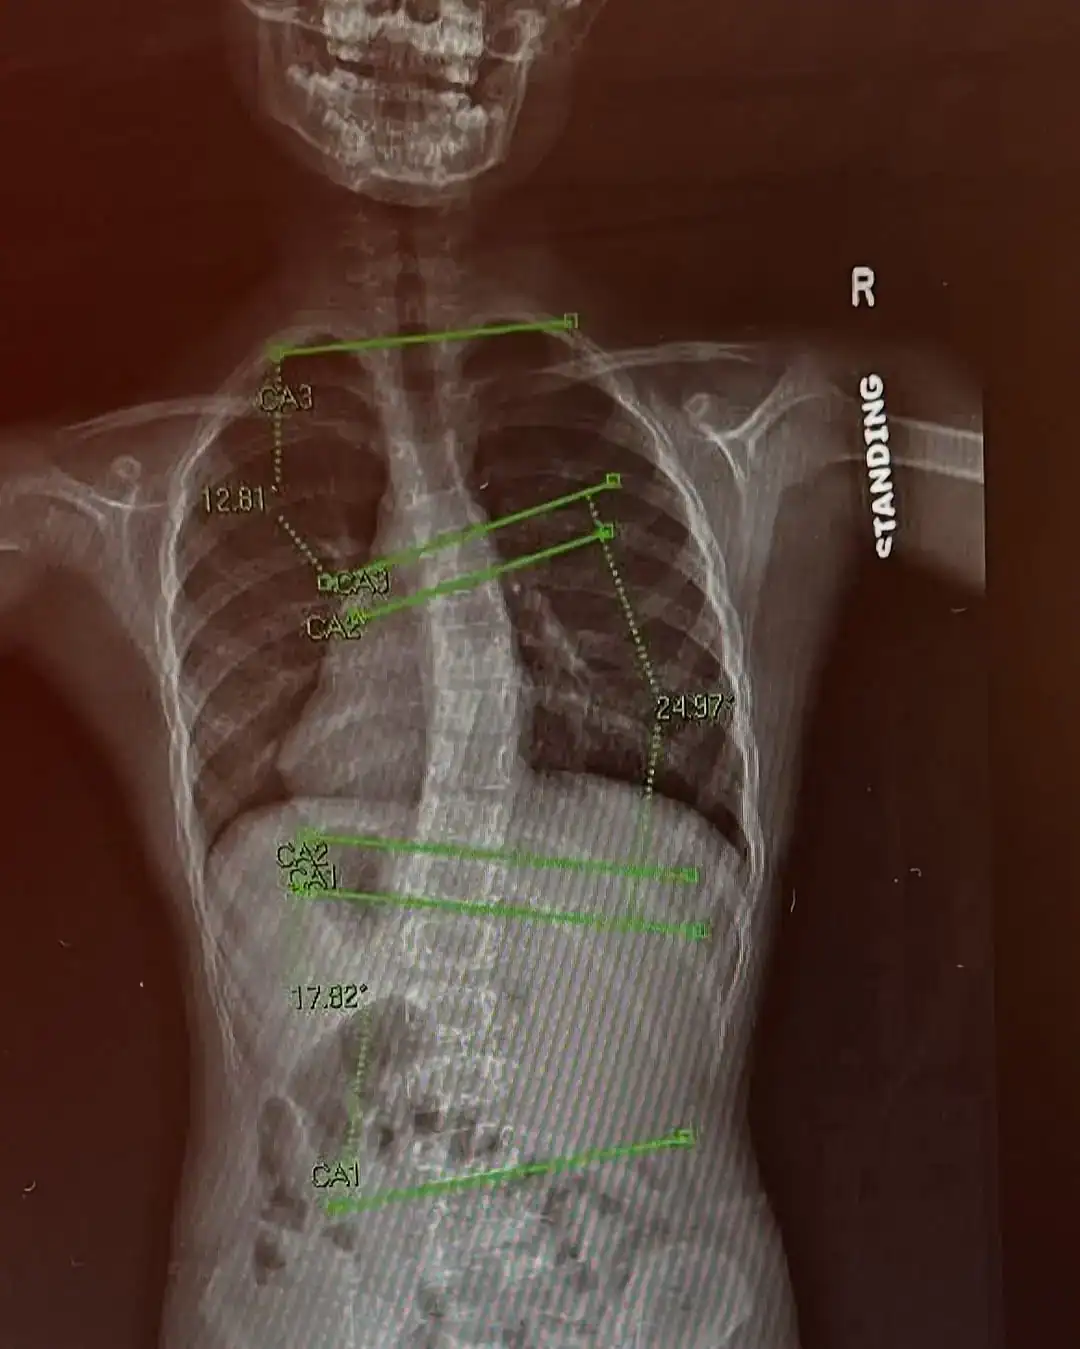

O diagnóstico de escoliose mudou a rotina da pequena Preslee Harris, de 7 anos, mas também se transformou em fonte de inspiração. Durante um exame de rotina no primeiro ano escolar, em maio de 2024, a pediatra pediu que a menina se curvasse para frente e percebeu um desvio na coluna. Exames de raio-X confirmaram o diagnóstico: escoliose, uma curvatura lateral da coluna que, no caso dela, apresentava 12 graus na parte superior, 17 no meio e 14 na inferior.

Com o encaminhamento para um ortopedista, veio a recomendação inicial de acompanhamento e novos exames após três meses. Mas, em agosto, o desvio já havia aumentado para 18 graus, o que levou os médicos a indicarem o uso de um colete ortopédico por 16 horas diárias.